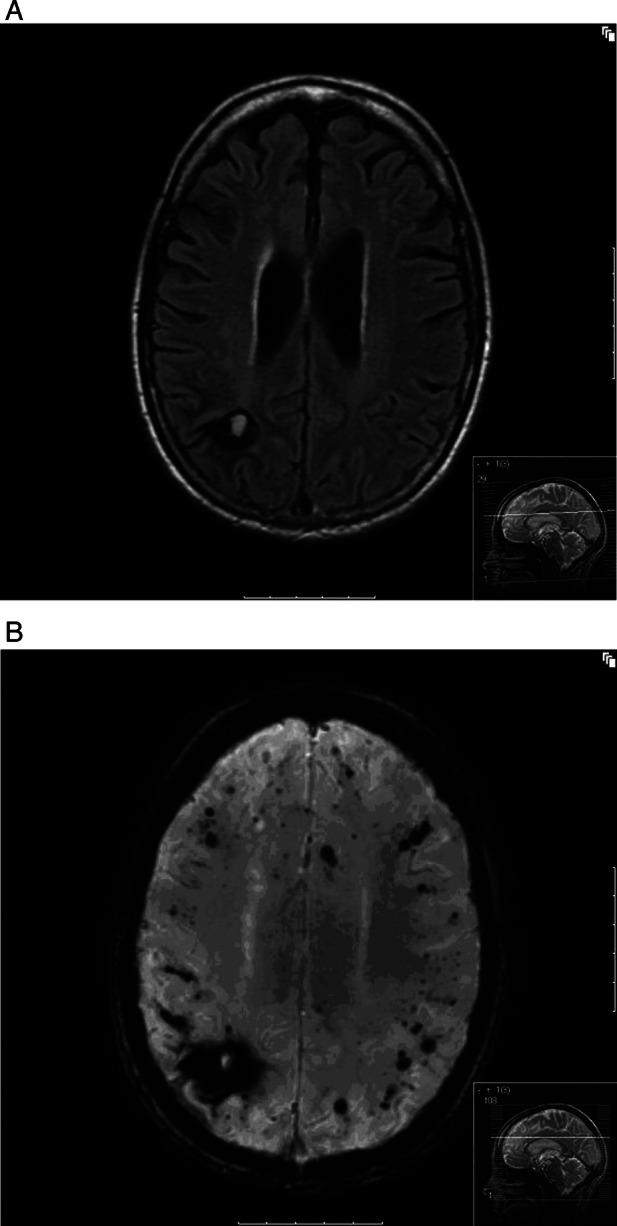

She was stepped down from ICU to the stroke unit 2 months after initial presentation and repatriated with tracheostomy to our unit 8 days later with rapid subsequent decannulation. Medically, she remained stable with normalisation of her blood parameters and normal observations. Surgical and tissue viability opinions were sought regarding her toes and sacral sore and rehabilitation was continued. Her imaging was reviewed with the neuroradiologists and MRI imaging undertaken at 3 months postevent to further characterise the brain lesions (figures 3).

Figure 3.

MRI brain undertaken at 3 months (A) fluid attenuated inversion recovery sequence. (B) SWAN sequence. Small area of evolving haemorrhage (subacute) in right parietal area. Multiple areas of microhaemorrhages in cerebral cortical and subcortical regions. SWAN, susceptibility-weighted angiography.